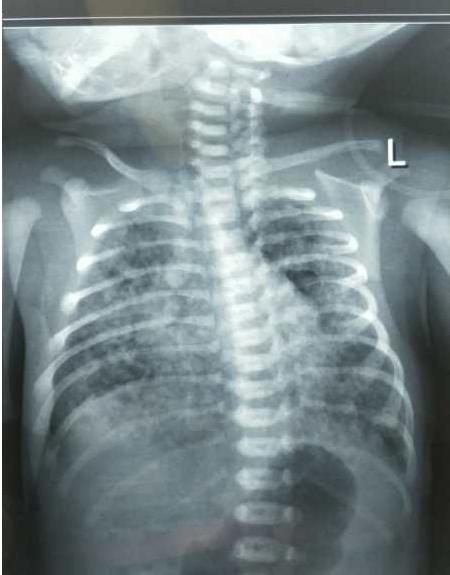

胸片显示双肺大量斑片状、粗颗粒状阴影伴肺气肿。结合病史,MAS诊断明确,随即进行插管、盐水气管内冲洗、滴入肺表面活性物质、上高频呼吸机等一系列急救处理。

下图是宝宝胸片的演变过程: